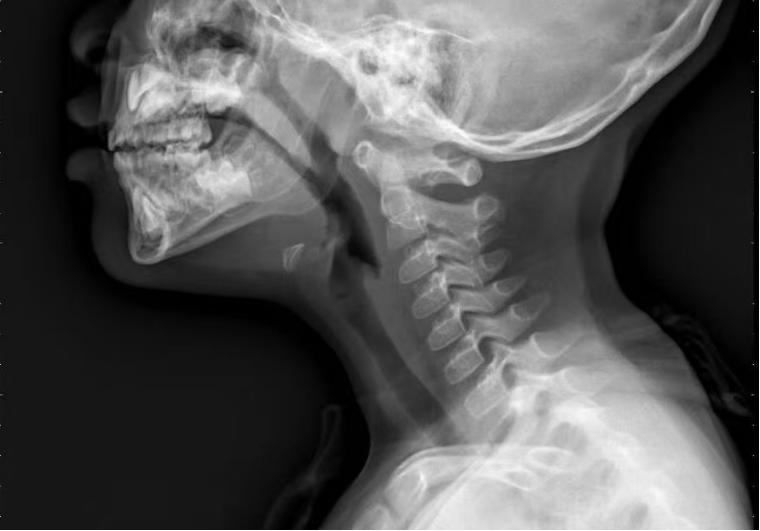

术前鼻咽侧位片

苏娟介绍,在检查方面,鼻内镜检查是诊断腺样体肥大的常用方法。这种方法可以直观地反映出腺样体肥大的程度,且创伤小,但需要儿童的配合。对于不配合的孩子,可以选择鼻咽X线检查。虽然这项检查有一定的放射性,但剂量非常低,在安全范围内。